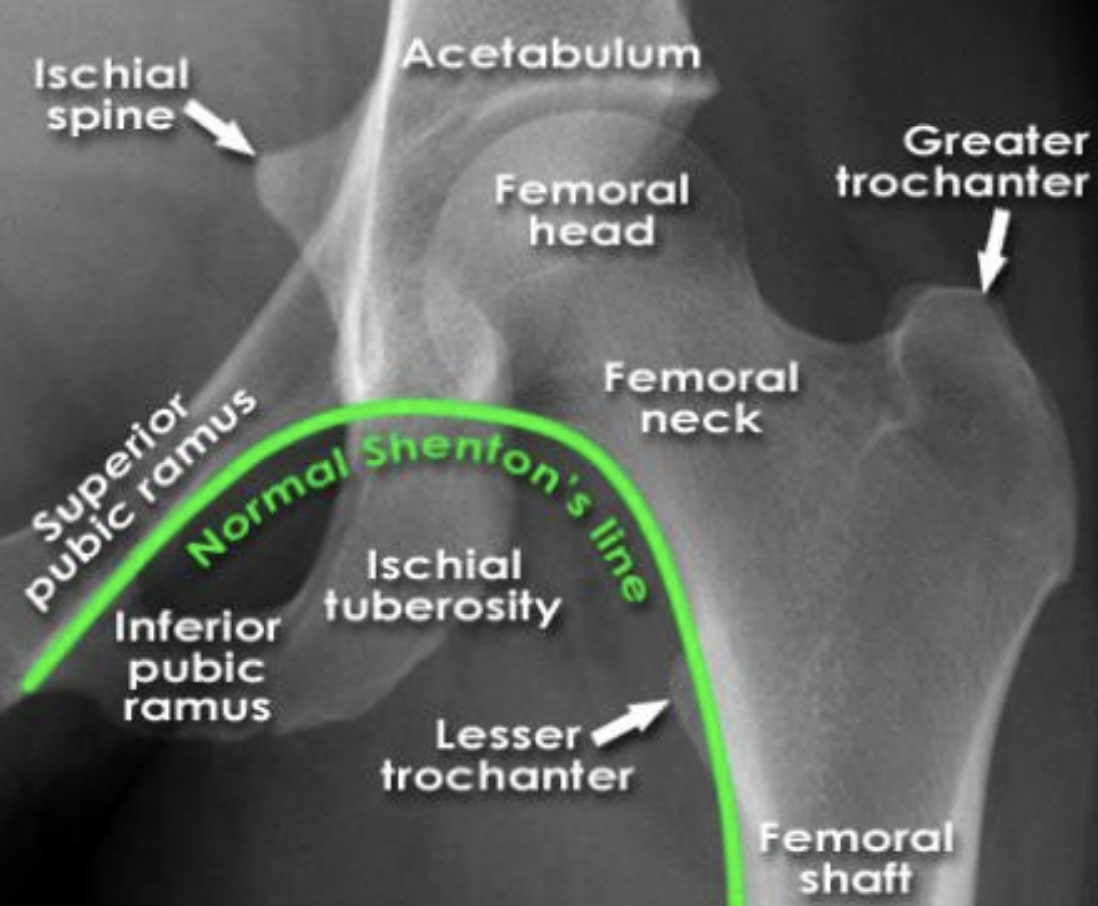

normal shenton’s line

lined formed by anatomical landmarks in a normal AP scan of a hip

intra-capsular vs extra-capsular classification

intracapsular: involving the head or neck of femur

fracture through neck of femur (most common in younger patients)

extracapsular: involving the femur excluding head or neck of femur

fracture through the trochanters

comminuted fracture (radiolucent) of the left proximal femur

intertrochanteric fracture (between the two trochanters)

extra-capsular classification

intracapsular fracture

65 year old male:

fall onto left side while getting out of bed

AP radiograph of the hip

Prior DXR (bone density) scan showed marked osteoporosis

(extracapsular classification)

radiolucent intertrochanteric fracture of the left proximal femur

or

radiolucent oblique fracture through the greater trochanter and neck of the femur on the left side